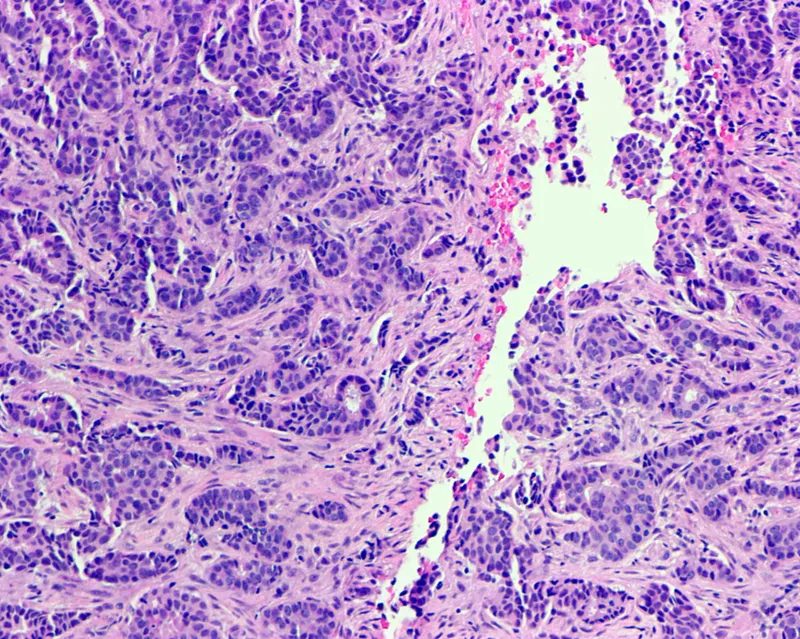

- Histology: Predominantly Invasive Ductal Carcinoma (IDC), >85% of cases.

- Lobular carcinoma is rare due to rudimentary terminal lobules in the male breast.

- Histology is almost always Infiltrating Ductal Carcinoma (IDC).